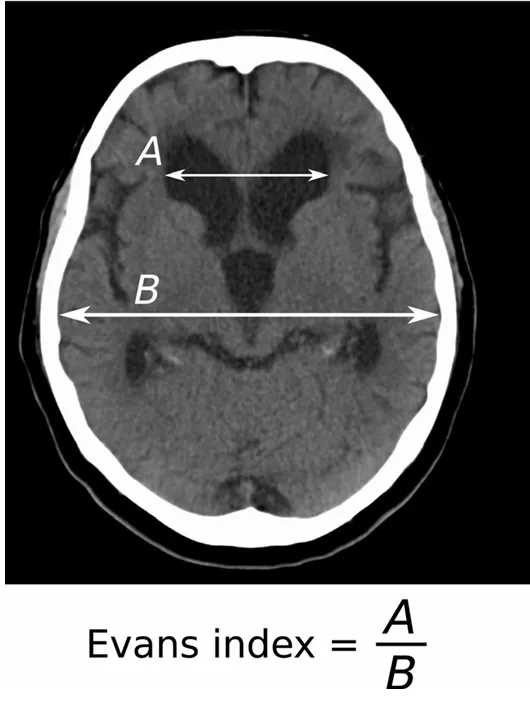

Evan’s index (A/B)

: NPH의 스크리닝 검사

A: frontal horns의 최대너비

B: 최대 두개내 너비

• 정상 : 0.2-0.25

• 0.3보다 큰 경우 뇌실 확장이 있다고 판단한다.